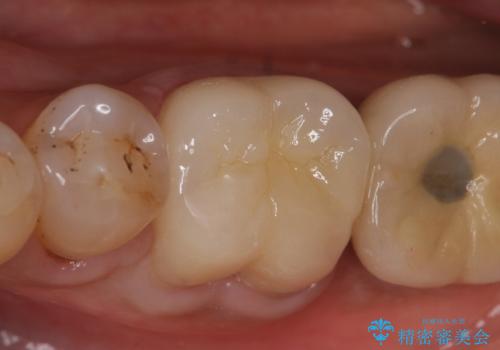

その後症状の消失を確認後、オールセラミッククラウンによる補綴を行いました。

今回用いたオールセラミッククラウンはジルコニアフレームという白い素材の上にセラミックを盛っているため、審美性が非常に高いのが特徴です。

また、ジルコニアは人工ダイヤモンドの材料にも使われているほど高い強度を持っており、そのためオールセラミッククラウンは審美性だけでなく、奥歯やブリッジの補綴も可能とするクラウンです。